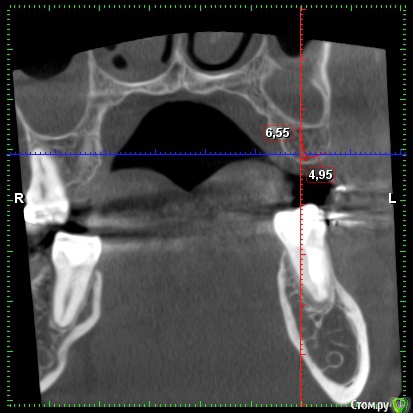

Bors Опубликовано 1 декабря, 2019 Автор Поделиться Опубликовано 1 декабря, 2019 по высоте хватает, ширину нужно смотреть на Кт (качать весь архив не буду) покажите срезы областей интересаСрезы сам не делал, так как не знаю насколько правильными они будут. Прикрепляю то, что получилось. как правило не влияетЯсно. Просто частенько проскакивает в описаниях тех или иных моделей информация о том, что это идеальный вариант при недостатке костной ткани и т.п. Не совсем понятно стоит ли переплачивать за тот же Nobel или выбрать что-то дешевле. Хочется поставить и забыть на всю жизнь про этот зуб. Ссылка на комментарий

red_butler Опубликовано 1 декабря, 2019 Поделиться Опубликовано 1 декабря, 2019 костная пластика не нужна, разве что небольшой закрытый синуслифтинг слева Ссылка на комментарий

Irouil Опубликовано 3 декабря, 2019 Поделиться Опубликовано 3 декабря, 2019 Что касается синус-лифтинга, то по 26-му зубу мне сообщили, что он действительно не нужен, а вот по 16-му что-то вроде пограничного положения. Все наоборот. Но синус лифт там требуется минимальный. Астра тёк прекрасные имплантаты Ссылка на комментарий